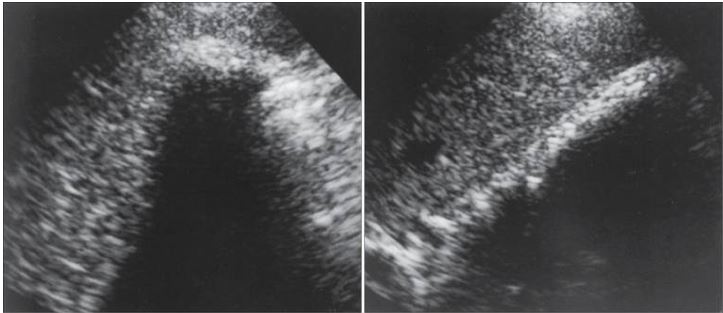

is uncommon cause for extrahepatic biliary obstruction as a result of an impacted stone in the cystic duct, which creates extrinsic mechanical compression of the common hepatic duct.

Patient presents with painful jaundice.

Mirizzi Syndrome